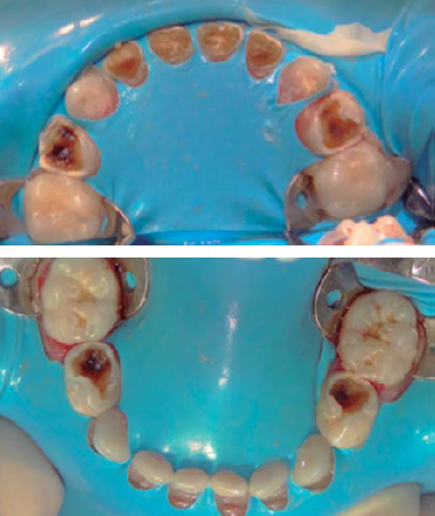

Se colocan los campos estériles de forma convencional y se aísla la totalidad de las arcadas con dique de hule (Figura 4), se realizan los siguientes tratamientos dentales: pulpotomías de primeros molares superiores, coronas de acero inoxidable en primeros molares superiores e inferiores, resinas en segundos molares inferiores, y selladores de fosetas y fisuras en segundos molares superiores.

Figura 4 Totalidad de los órganos dentarios aislados al momento de la intervención bajo anestesia general.

Debido a que la paciente cursaría con un tratamiento de quimioterapia que la inmunosuprimiría, importantemente se decide realizar las extracciones de los incisivos centrales y laterales superiores preventivamente para evitar el riesgo latente de infección odontogénica que pueda agravar su estado de salud y no se indica en este momento la colocación de ninguna aparatología estética que reemplace los órganos dentarios extraídos pues dicha aparatología puede actuar como reservorio de bacterias que en un momento determinado podrían complicar su evolución clínica (Figura 5).